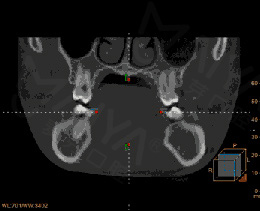

正畸治疗的关键在于诊断、及对治疗结果的预测。麦芽口腔数字化正畸科认为,当口内数据量化到毫米级甚至微米级,最有利医生对方案作出精准判断与调整,所以成功落地深圳首家全数字化口腔正畸科室,致力更严谨、精准、精密的矫牙疗效!

• 德国KAVO锥形束CT

高精度重建三维图像具有指导意义